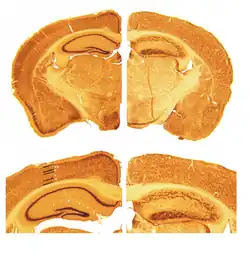

Das Gehirn von Reeler-Mäusen unterscheidet sich makroskopisch und mikroskopisch bedeutend von dem normaler Mäuse. Das Kleinhirn ist deutlich in seiner Größe reduziert (ca. −30 %) und zeigt bei mikroskopischer Betrachtung nicht die typische Laminierung in unterschiedliche Zellschichten. Die Großhirnrinde (lat. Cortex) und der Hippocampus sind ebenfalls stark in ihrer zellulären Architektur verändert. Während im normalen Gehirn der Cortex üblicherweise in sechs Schichten unterteilt werden kann, schien es anfangs so, als sei diese Schichtung bei Reeler-Mäusen völlig aufgehoben.[10]

Es wurde jedoch gezeigt, dass die kortikale Schichtung bei der Reeler-Maus keinesfalls komplett aufgehoben ist, sondern dass sie vielmehr auf dem Kopf steht.[11] D. h. Nervenzellen, die normalerweise in den tiefen Schichten des Cortex liegen, finden sich in der Reeler-Maus weiter in Richtung Hirnoberfläche und umgekehrt. Dieses Phänomen steht in direktem Zusammenhang mit der Funktion des „Reelin“-Proteins während der embryonalen Entwicklung. Obwohl über den genauen Modus in Fachkreisen noch gestritten wird, ist allgemein anerkannt, dass Reelin als Signalmolekül die Wanderung von Neuronen während der Entwicklung des Gehirns beeinflusst. Die Abwesenheit von Reelin im Hirn der Reeler-Maus führt daher zu gestörter neuronaler Migration.